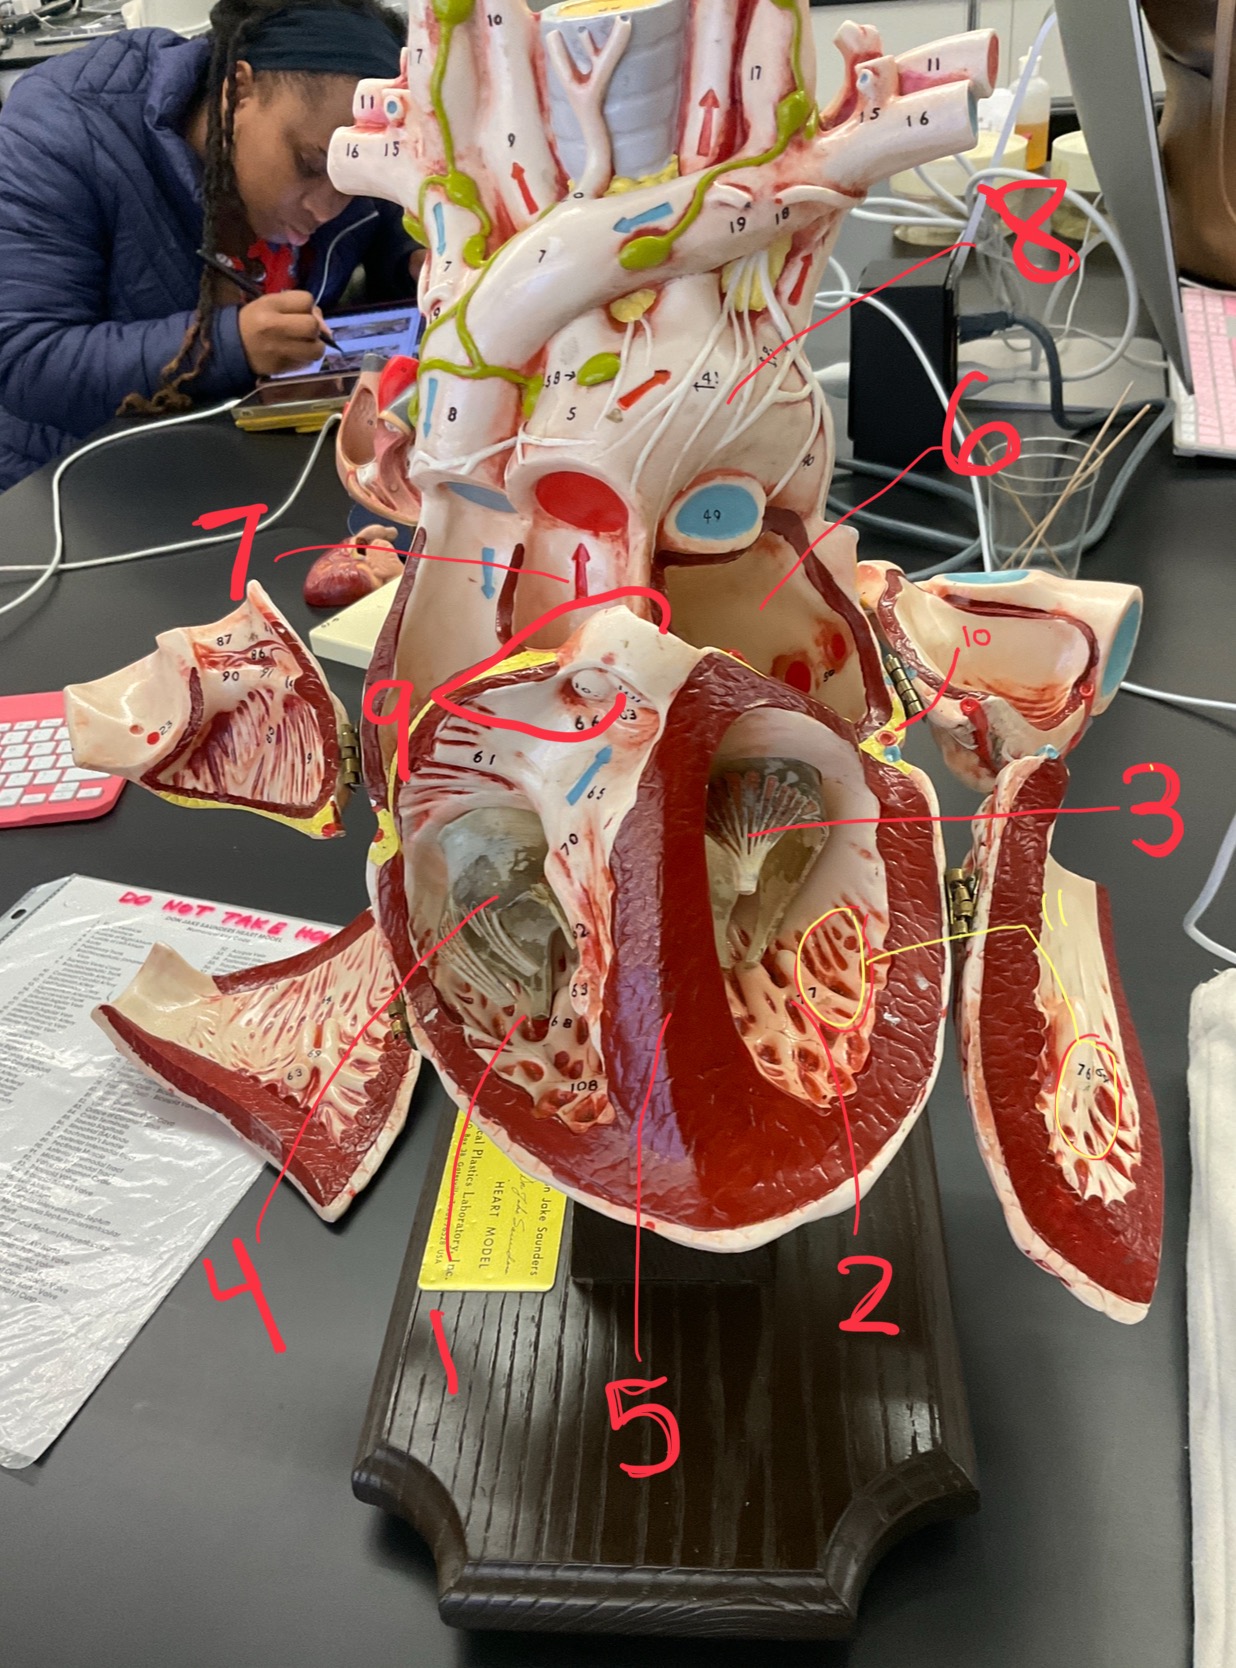

1

epicardium

2

3

endocardium

3

2

myocardium

4

1

coronary sinus

5

2

inferior vena cava

6

3

superior vena cava

7

1

right ventricle

8

2

left ventricle

9

3

bicuspid

10

4

tricuspid

11

5

interventricullar septum

12

6

left atrium

13

7

aorta

14

8

aortic trunk

15

9

pulmonary semi-lunar valve

16

10

atrevoventricullar sulus

17

11 (not smooth part)

trubeculae carneae

18

1

papillary muscle

19

2

chordae tendineae

20

4

pulmonary trunk

21

6

aortic trunk